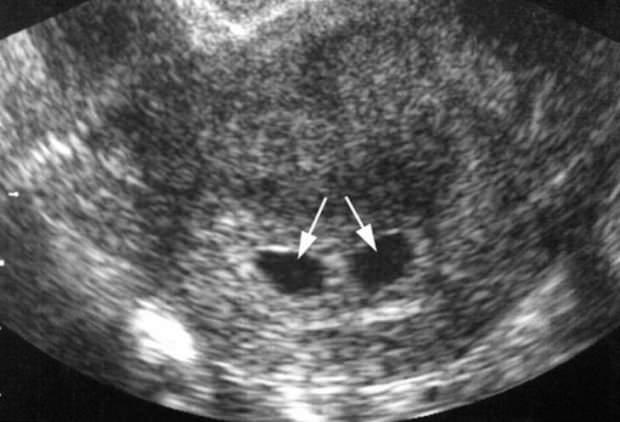

İkizin türüne göre olumlu ya da olumsuz sonuçlanan ikiz gebelikte eğer bahsedilen ikizlik, tek yumurta ikizlerine ait ise kişinin kendisinde ya da ailesinde ikiz bulunmasının hiçbir etkisi yoktur. Nedeni ise döllenme esnasında tek bir yumurtanın ikiye bölünmesidir. Bu durum tesadüf olarak gerçekleştiği için ikiz gebelik şansı artmaz. Ancak çift yumurta ikizlerinde istisna! Bir defada iki adet yumurtanın atılması ve ikisinin de ayrı ayrı döllenmesi genetik olarak aktarılabilir.

İkiz kadının kendi hamileliğinde değilde bir nesil atlayarak torunlarında ikiz gebelik olasılığının daha fazla olacağı görüşü doğru değildir. Çift yumurta ikizinde erkek, eşinin yumurtlama sayısını etkileyemeyeceğinden aktaramaz. Dolayısıyla ikiz kadın kendisi de ikiz çocuk doğurabilir.